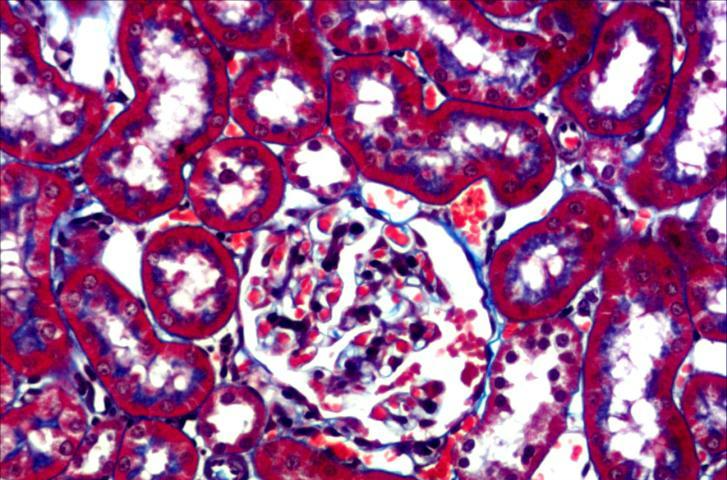

Masson染色(MT染色)是結締組織染色中最經典的一種方法,又稱馬松染色,是顯示組織中纖維的主要方法之一,是膠原纖維染色權威而經典的技術方法。

該法染色原理與陰離子染料分子的大小和組織的滲透有關,分子的大小由分子量來體現,小分子量易穿透結構致密、滲透性低的組織;而大分子量則只能進入結構疏松的、滲透性高的組織。

然而,淡綠或苯胺藍的分子量都很大,因此Masson染色后肌纖維呈紅色,膠原纖維呈綠色或藍色,主要用于區分膠原纖維和肌纖維。